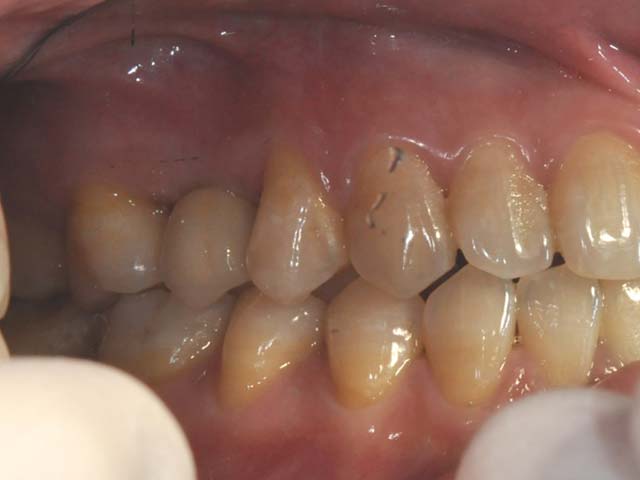

齒槽骨保存術+植牙 首頁 案例分享 人工植牙 齒槽骨保存術+植牙 STEP1拔除掉無法使用的斷裂牙根 STEP2齒槽骨保存術—使用骨粉填補拔牙傷口 術前 V.S 術後 植牙第一階段—植入牙根 植牙第二階段—製作正式假牙